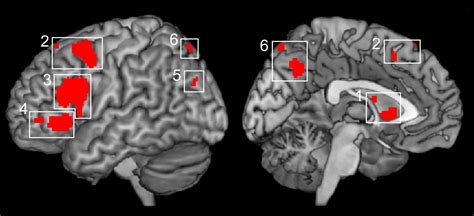

La ricerca condotta da studiosi come E. Paulesu e i suoi collaboratori ha significativamente ampliato la nostra comprensione delle basi neurali di diversi processi cognitivi e comportamentali. I loro studi, pubblicati su riviste scientifiche di alto profilo come Nature, Science e PNAS, hanno esplorato una vasta gamma di argomenti, tra cui:

- Basi neurali della memoria di lavoro verbale: Dimostrando come specifiche aree cerebrali supportino la componente verbale della memoria di lavoro.

- Effetti culturali sul cervello: Evidenziando come fattori culturali possano influenzare l'elaborazione cerebrale di determinati stimoli.

- Dislessia e unità biologica: Esplorando la diversità culturale e l'unità biologica sottostante la dislessia.

- Consapevolezza motoria e controllo motorio: Mostrando la sovrapposizione anatomica tra la consapevolezza motoria e il controllo del movimento.

- Basi neurofunzionali dell'azione intenzionale: Dissezionando i meccanismi cerebrali che sottendono l'azione volontaria.

Questi studi, attraverso l'uso di metodologie strumentali avanzate, hanno fornito prove concrete su come il cervello elabora informazioni, genera emozioni, controlla il movimento e come queste funzioni possano essere alterate in diverse condizioni patologiche. La ricerca sull'obesità, ad esempio, ha rivelato come aree cerebrali coinvolte nella motivazione e nell'elaborazione visiva degli stimoli alimentari presentino una connettività funzionale alterata, contribuendo a una migliore comprensione dei meccanismi alla base del desiderio patologico di cibo.

L'integrazione delle conoscenze provenienti da diverse tecniche di neuroimaging e dall'elettrofisiologia è fondamentale per costruire una comprensione olistica della mente umana e per sviluppare interventi efficaci volti a migliorare la salute cognitiva e il benessere.